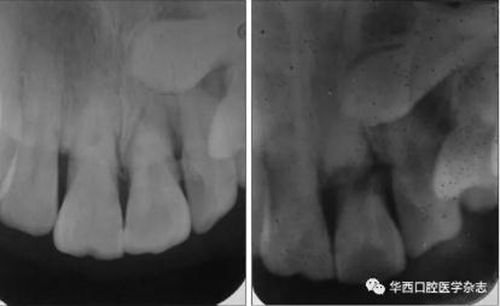

(1)變換角度X線投照的必要性。有些冠根折在行正常角度攝片時不易被發(fā)現,變換角度再次攝片則可能被發(fā)現(圖1)。

左:未見根折;右:可見根折。

圖 1 21變換X線投照角度根尖片